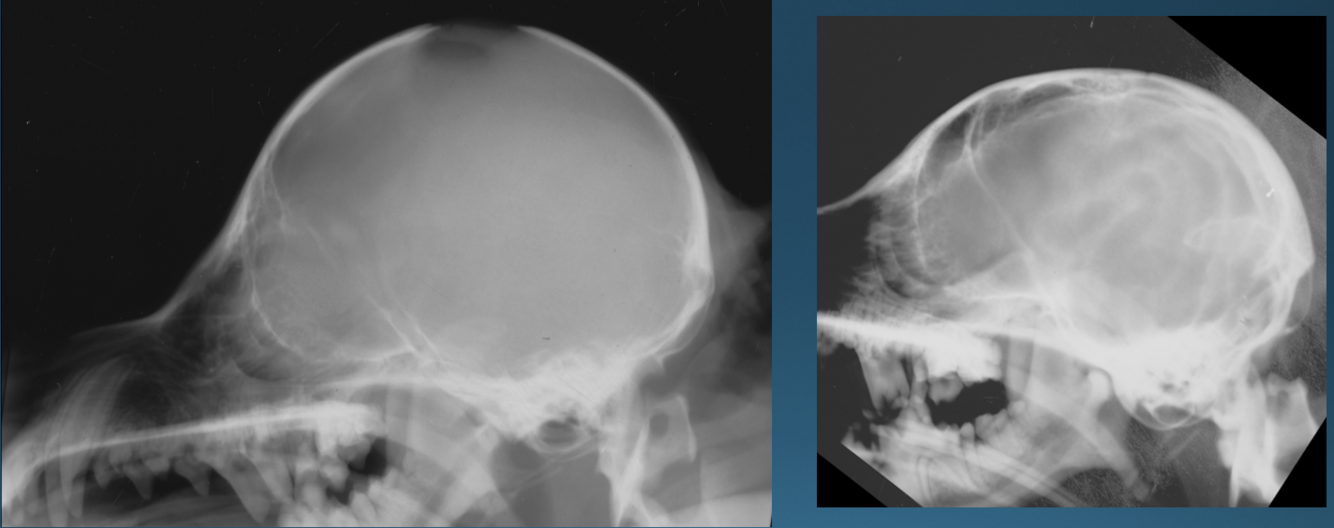

Q

What is shown in these images?

A

Left:

-decreased prominence of internal convolution marks on calvarium due to hydrocephalus

Right:

-normal